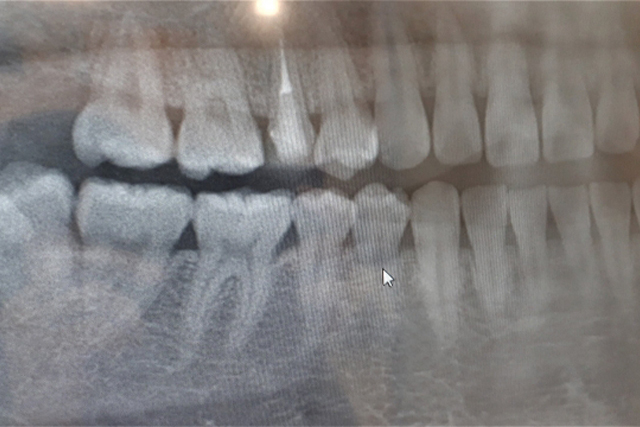

親知らずの抜歯は、大きい病院の口腔外科に紹介されるケースが多いですが、当院ではできるだけ当院で抜歯を行い、患者様の負担を軽減することを心がけています。